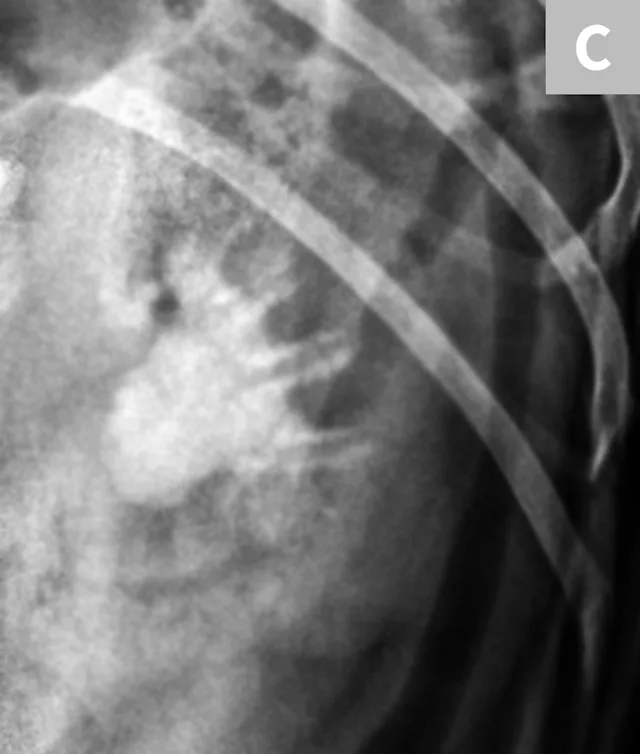

Differentiation between a complete vs partial ureteral obstruction can be difficult with survey radiography and ultrasonography alone. Antegrade pyelography (nephropyelocentesis with renal pelvic injection of iodinated positive contrast medium using ultrasound guidance) may be useful for documenting a complete vs partial obstruction (Figure 7).11

FIGURE 7A

Lateral abdominal radiograph of a cat with multiple, small, oval mineral opacities superimposed over the ventral aspect of the retroperitoneal space (arrows). These mineral opacities are arranged linearly extending from the caudal aspect of the kidneys to the level of the urinary bladder.

Antegrade pyelography is beneficial when compared with standard IV urography, as it lowers the risk of potential contrast-induced renal damage and provides excellent filling of the renal collecting system, regardless of renal function.11